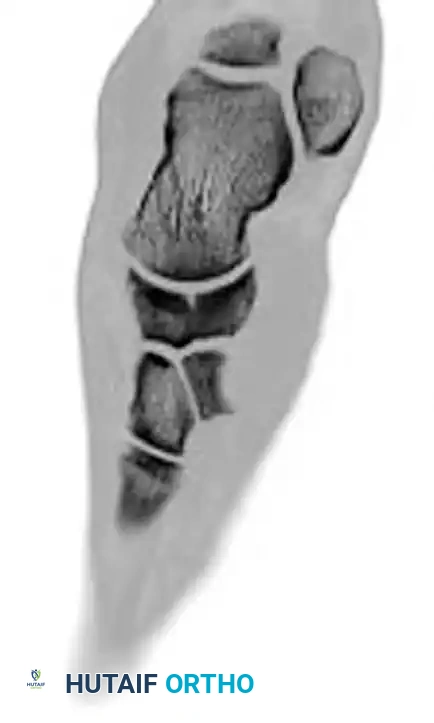

Fractures of the tarsal navicular body are classified into three distinct types based on the Sangeorzan classification system. The primary surgical goals for displaced fractures are the restoration of articular congruity and the maintenance of medial column length.

- Type I: The fracture line occurs in the coronal plane, creating a dorsal fragment that usually consists of less than 50% of the navicular body. Anteroposterior radiographs may only show a subtle double cortical shadow at the joint line.

- Type II: The primary fracture line is sagittal or oblique. The talonavicular joint is most often subluxated dorsally and medially, accompanied by adduction of the forefoot.

- Type III: Characterized by severe comminution of the navicular body. This is frequently associated with disruption of the cuneiform-navicular joint, lateral deviation of the forefoot, and concomitant injuries to the cuboid or the anterior process of the calcaneus.